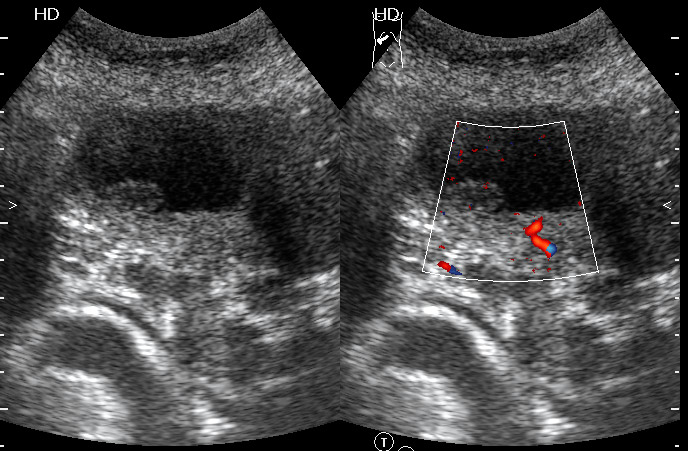

Рак желчного пузыря #2

Женщина - пенсионерка. Жалобы скудные, дискомфорт в правом подреберье.